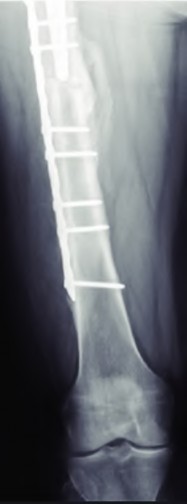

A 72-year-old female presents with progressive left thigh and knee pain for the last year. 5 years ago she sustained a femoral neck fracture treated with the implant seen in Figures A-C (current radiographs). The thigh pain is worse with weight-bearing. C-reactive

protein and erythrocyte sedimentation levels are within defined limits. Which of the following is the most likely cause of her pain?